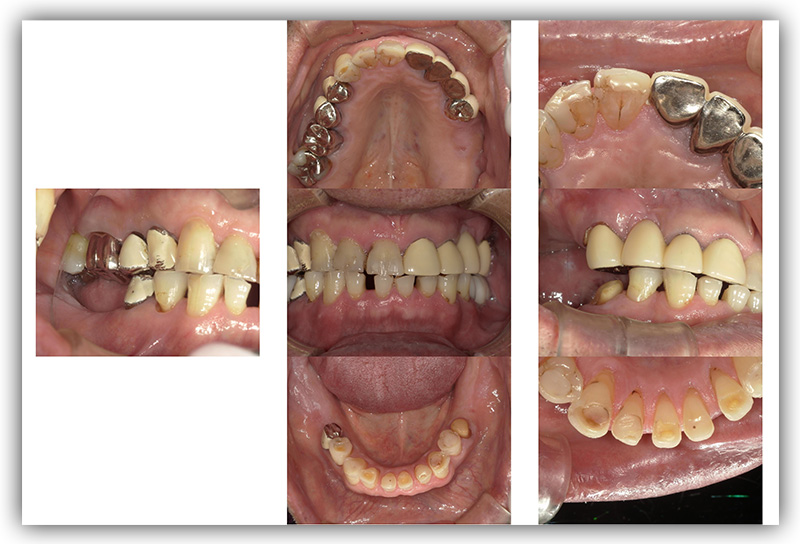

CASE_03

40代女性(インプラント)

- 患者さん情報(年齢・性別)

- 40代 女性

- 主訴

- 被せものをインプラントにしたい

- 治療箇所

- 2箇所

- 治療方法

- インプラント

- 費用

- 84万円

- 治療期間

- 約半年